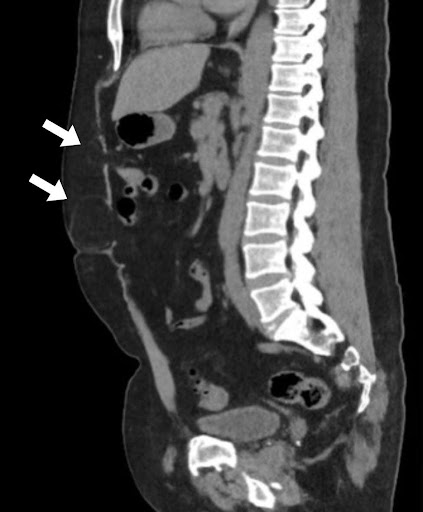

पेट और श्रोणि के गैर-विपरीत बढ़ाया सीटी ने अक्षीय इमेजिंग पर दो वसा युक्त मिडलाइन हर्निया दोषों का प्रदर्शन किया। यूरोपीय हर्निया सोसाइटी (ईएचएस) वर्गीकरण के अनुसार, ये एक एम 2 हर्निया के अनुरूप हैं जो चौड़ाई में 16 मिमी और क्रानियोकौडल लंबाई में 8 मिमी मापते हैं, और एक एम 3 हर्निया की चौड़ाई 37 मिमी और लंबाई में 30 मिमी है। धनु पुनर्निर्माण ने अतिरिक्त फेशियल दोषों के साथ-साथ पूर्व मिडलाइन चीरा के साथ क्षीण प्रावरणी के क्षेत्रों का खुलासा किया, जो सबक्लिनिकल हर्निया के अनुरूप था।

चित्रा 1 अक्षीय छवियों पर वसा युक्त एम 2 और एम 3 हर्निया को दिखाता है। धनु विचार पैथोलॉजी का अधिक व्यापक चित्रण प्रदान करते हैं, M1-M3 क्षेत्रों में फैले क्षीण प्रावरणी का प्रदर्शन करते हैं, अतिरिक्त इंटरपेरिटल हर्निया दोषों (धराशायी तीर) का विचारोत्तेजक फेशियल उतार-चढ़ाव, और M2 ज़ोन (तीर) से बेहतर एक छोटा हर्निया दोष जो अक्षीय इमेजिंग पर स्पष्ट नहीं था।

चित्रा 1. अक्षीय और धनु विचारों के साथ सीटी पेट और श्रोणि। सीटी इमेजिंग मिडलाइन वसा युक्त हर्निया दोषों का प्रदर्शन करती है।